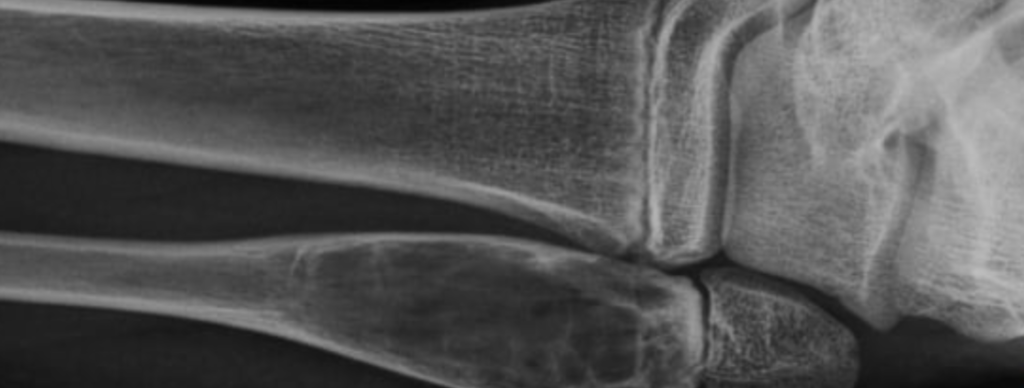

Fratura subperiostal